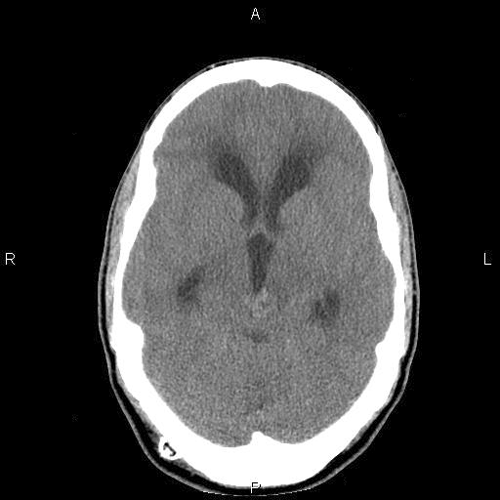

Imaging:

A poorly defined lesion is identified in the pineal region of the CT scan. The increased density suggest calcifications (Panel A). A moderate degree of hydrocephalus is also present (Panel B).

On MRI studies, pineal germinomas and primary pineal tumors are usually isointense to gray matter on T1-weighted, are slightly hyperintense on T2, and have strong homogenous enhancement. Intratmuoral cysts can occur as well. CT scan shows the lesion as a hyperdense mass that surrounds a calcified pineal gland. The neuroimaging characteristics of germinomas and nongerminomatous germ cell tumors are similar enough to limit diagnostic certainty, and either tissue confirmation or the measurement of specific tumor markers is needed for diagnosis. Pineal calcification on plain radiographs, uncommon in children less than 10 years of age, is a useful clue to the diagnosis of a germ cell tumor, since approximately 70% of patients with pineal region tumors have calcifications 1. The calcifications in germinoma surround the pineal gland as the germinoma grows. In contrast, pineocytomas commonly have intratumoral calcifications. Unlike germinomas, teratomas typically have heterogenous MRI signals because they can contain tissue from all 3 germinal layers.